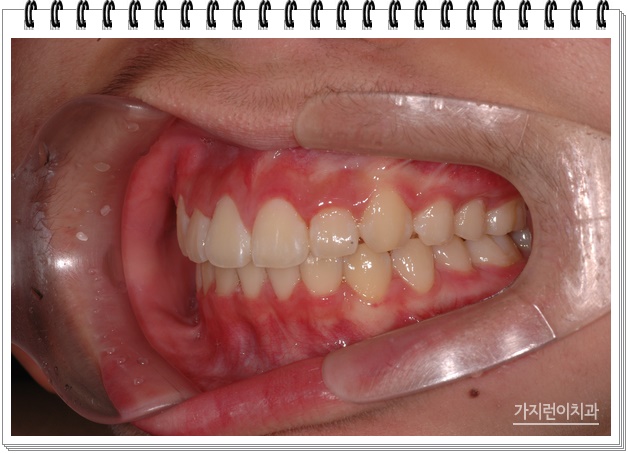

여기에 성장기 아이들의 경우 헤드기어를 이용한 교정도 이용해볼 수 있습니다. 성장기 돌출입에는 꼭 착용해야 하는 장치인데요. 보기에는 불편해보이지만 성장 속도나 방향을 원하는 쪽으로 조절할 수 있기 때문에 잘 활용하는 것이 추가장치를 이용할 필요없는 합리적인 방법이라고 할 수 있겠습니다. 이후 꾸준한 관리를 하게 된다면

위와 같은 모습을 얻어볼 수 있는데요. 성장기라는 시기를 잘 이용해 뼈 성장을 조절하고 미니 스크류를 동한 상악의 후방 이동을 진행한 것이죠. 그렇다면 성장기에 할 수 있는 교정은 이것 뿐일까요?